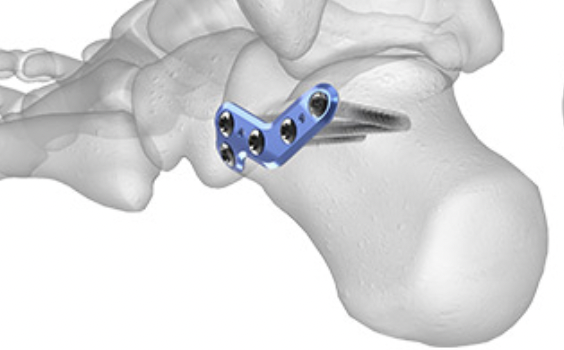

Minimally invasive surgery via sinus tarsi approach

Arthrex MIS calcaneal plating system

Acumed MIS calcaneal plating system

Technique

Use lateral plate with minimally invasive techniques